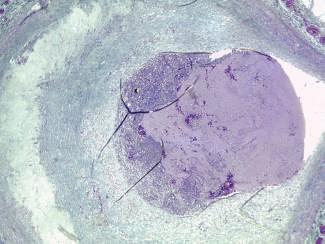

indivíduos a identificar podem ser indivíduos vivos ou ca dáveres, sendo, no caso destes últimos, as situações mais comuns as dos cadáveres esqueletizados (Figura 60.1). Genericamente, no que se refere aos cadáveres presentes para identificação genética de desconhecidos, as situações mais frequentes na rotina pericial dos serviços médico-le gais resultam quer de mortes naturais por doença ou por outros fatores intrínsecos ao indivíduo, quer de mortes vio lentas, nas quais incluímos os suicídios, os homicídios e os acidentes, sejam estes, acidentes rodoviários, incêndios, explosões, derrocadas, naufrágios ou outros.

Para além de indivíduos vivos ou cadáveres para identifica ção genética de desconhecidos no âmbito das situações até aqui elencadas, os serviços médico-legais recebem, ainda, para identificação genética, remanescentes de inter rupções de gravidez (Figura 60.2), fetos ou remanescentes fetais (Figura 60.3), recém-nascidos, bem como amostras biológicas que classificamos como amostras dúbias.

Fig. 60.1 Corpo esqueletizado, para identificação Fig. 60.2 Remanescentes de interrupção da gravidez, para identificação do pai biológico